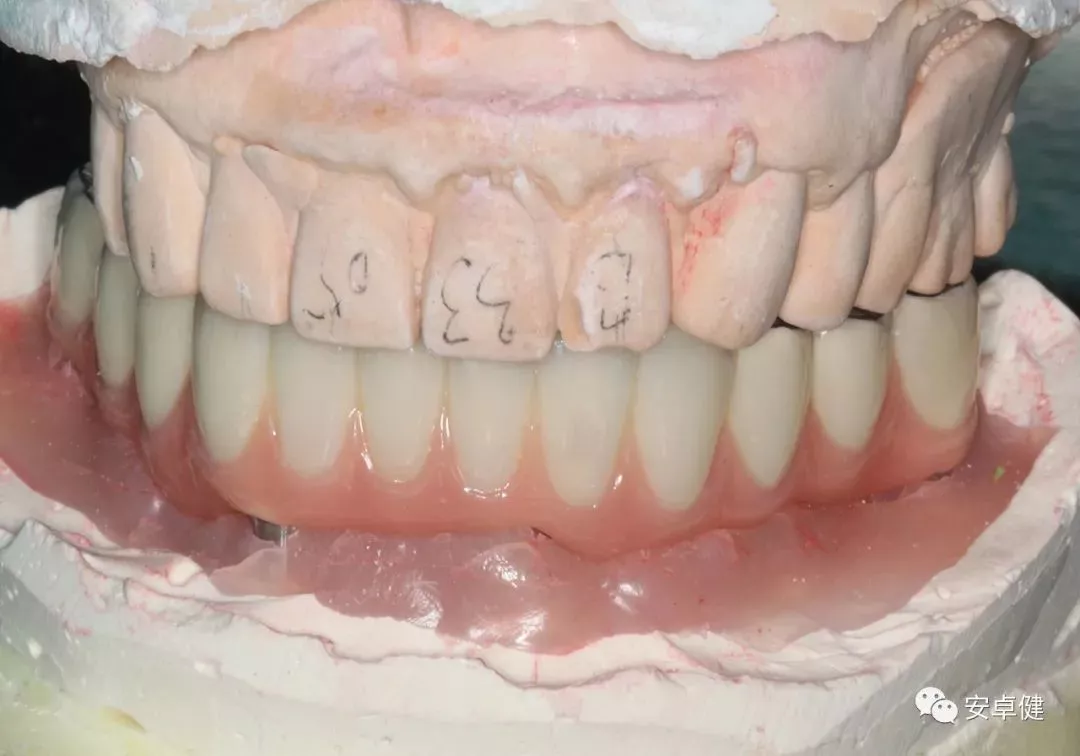

▷ 最终修复体制作

• 由于疫情原因,术后16个月制取最终修复体印模;

最终修复体蜡型合面照

• 制作最终修复体蜡型,分别于架及口内试戴检查其外形及咬合;

最终修复体蜡型上架正面观

最终修复体蜡型上侧面观

试戴最终修复体蜡型正面照

试戴最终修复体蜡型侧面照

试戴最终修复体蜡型合面照

• 完成最终修复体制作。